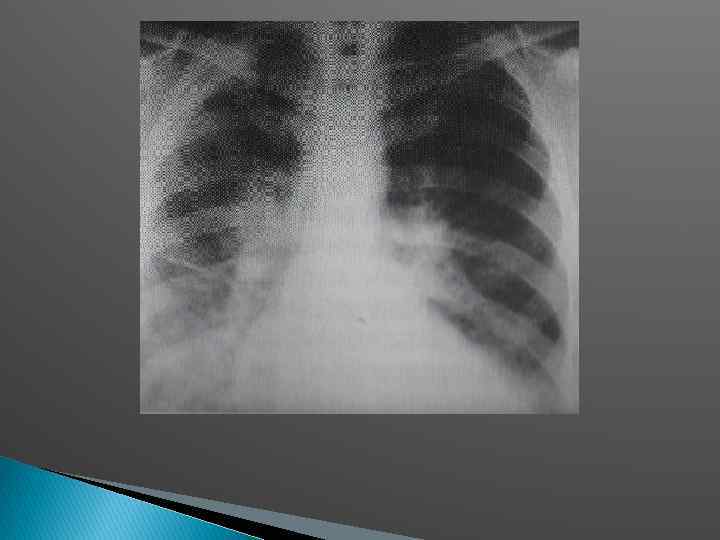

Ячеистая деформация легочного рисунка: медицинская визуализация